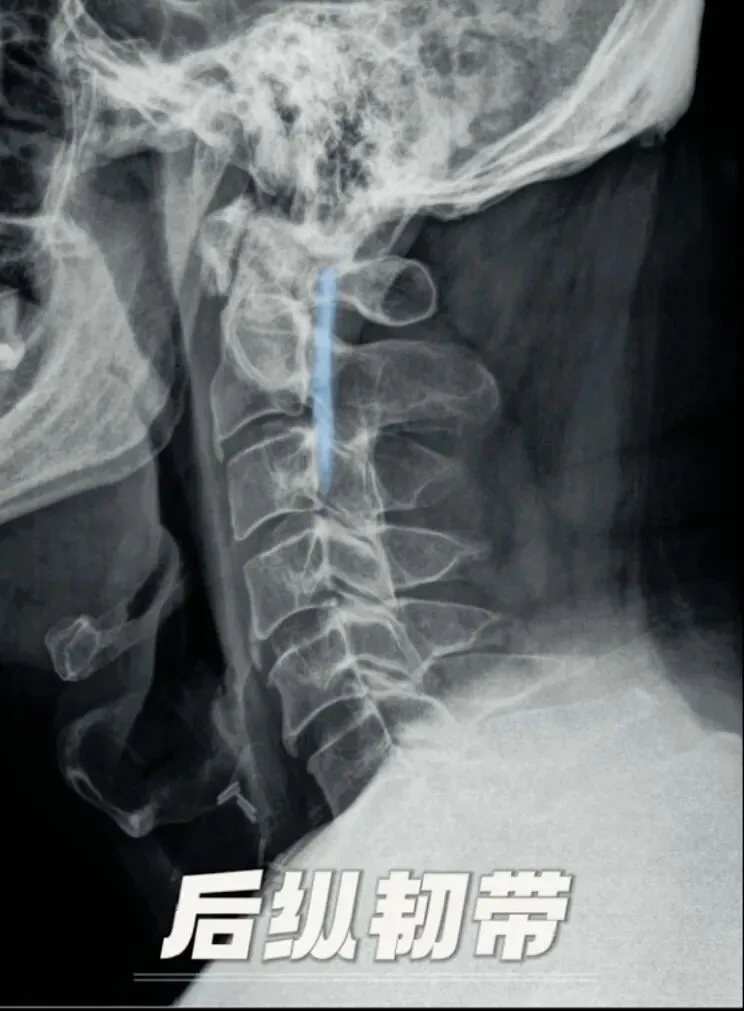

再其次是后纵韧带,位于椎管内椎体的后面,窄而坚韧,起自枢椎,并与覆盖枢椎椎体的覆膜相续下达骶骨,有限制脊柱过度前屈的作用。

当这条韧带因为未知的原因悄然钙化增厚,最终异化成坚硬的骨铠甲时,他便从保护者转变为潜在的压迫者。

这便是颈椎后纵韧带骨化特征,是颈椎后纵韧带组织被异位骨组织替代,形成沿椎体后缘分布的条索状或斑块状骨化灶,这些骨化灶如同在椎管内壁生长的肿物,逐渐侵占空间,压迫脊髓与神经根,常与弥漫性特发性骨肥厚共同存在。